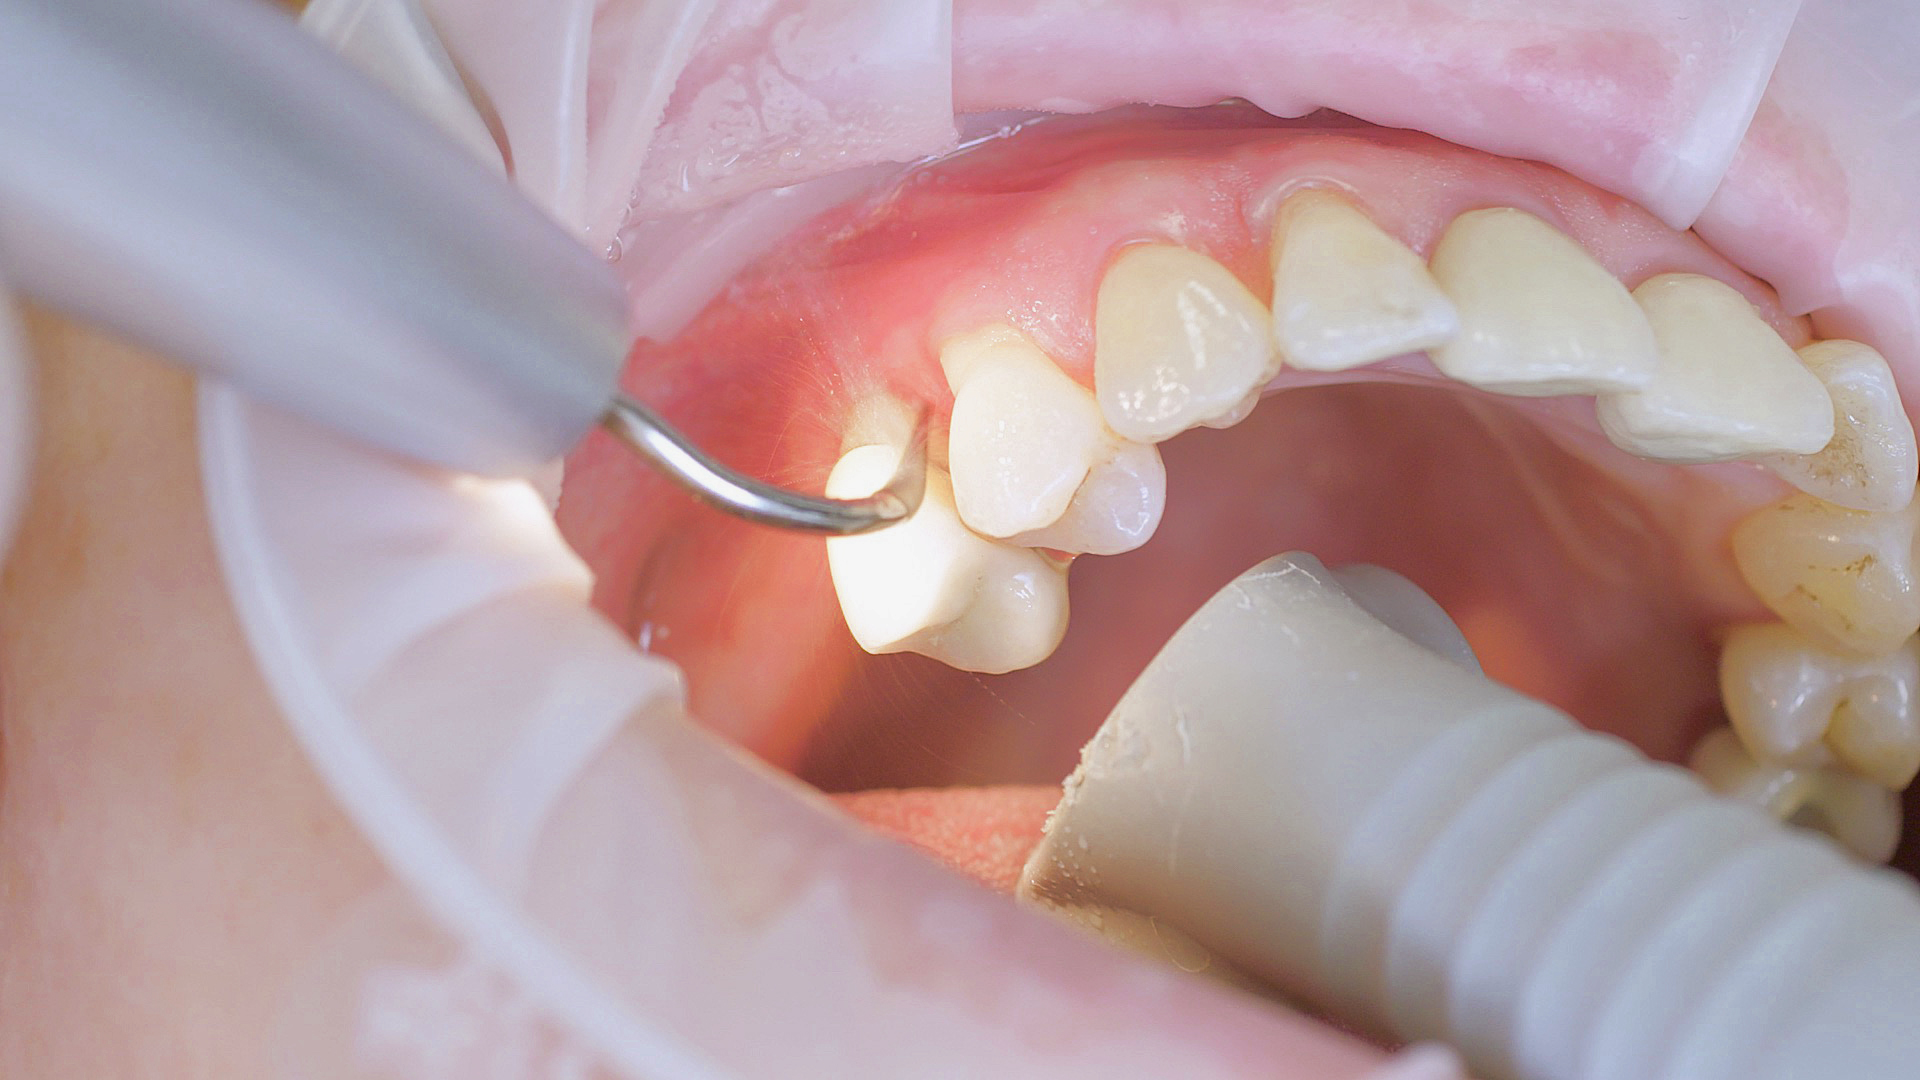

Every dental examination is based on a detailed medical history combined with targeted diagnostics con- taining as much detail as possible: The dentist records systemic risk factors such as diabetes or smoking and identifies any potential increased tendency to inflammation.[3] Hard and soft tissues are examined and periodontal pockets are probed in a screening test according to PSR (Periodontal Screening and Recording). In case of abnormal findings, the periodontal status is then re- corded and therapy is initiated where necessary. This treatment begins with professional biofilm management, by using, for example, rotary cups and polishing com pounds (Fig. 1), and comprehensive instructions in oral hygiene. Sonic or ultrasonic systems remain an effective alternative or supplement to manual instruments for sub- gingival debridement and biofilm management (presentation by Prof. Dr Ulrich Schlagenhauf; Fig. 2). Supplementary use of photodynamic therapy, air polishing or local and systemic antibiotics is not adequately documented (Prof. Dr Sema Hakki).[4] According to Dr Sergio Bizzarro, improved biomarker diagnostics may lead to an increase in customised patient therapy in the future.

An air scaler efficiently performs the initial debridement

Fig. 2: An air scaler efficiently performs the initial debridement, as part of initial periodontal therapy.